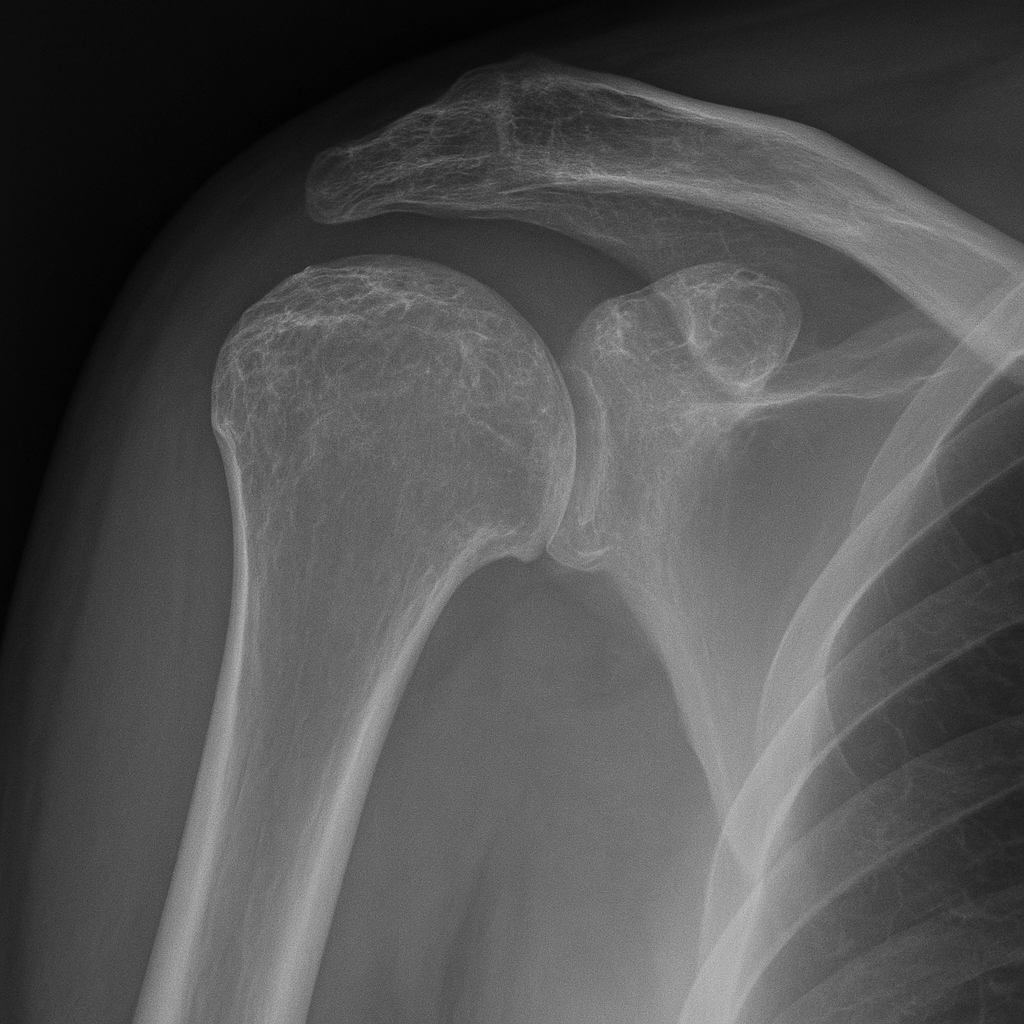

- Röntgen: az ízületi rés beszűkülése, osteophyták, csontmegvastagodás látható.

- MRI, CT: pontos képet ad a porc és a rotátorköpeny állapotáról.